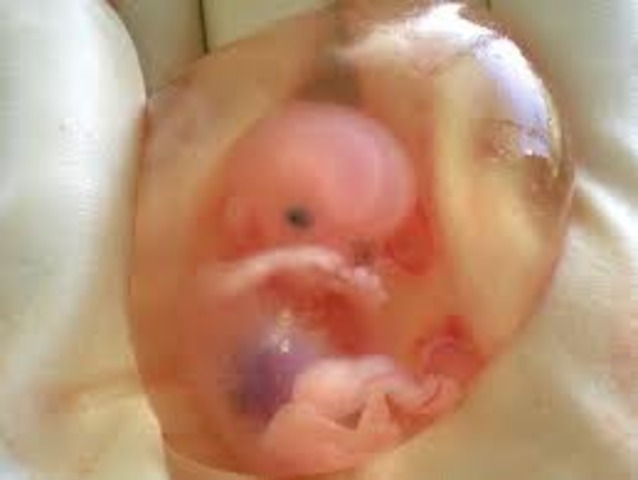

• 7 weeks pregnant

7 weeks pregnant

Hands and feet are emerging from developing arms and legs.Your baby is still considered an embryo and has something of a small tail, which is an extension of her tailbone. Your baby has doubled in size since last week and now measures half an inch long.